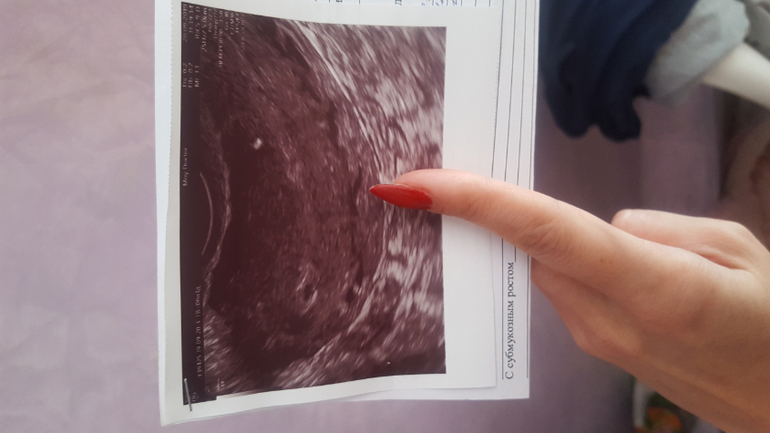

Девочки, добрый день. У кого было так же? Чего ждать? Ситуация у меня такая. Мы с мужем как и все, планируем детей , поэтому тесты мы покупаем постоянно. Последняя менструация была 6.08.19 , но месячные пришли раньше на 5-6 дней, цикл у меня 27-28 дней. Вообще, я их ждала числа 11-12. Отталкиваясь от месячных 6.08 , в сентябре я ждала их приход 2 числа , ну максимум 6. Они не пришли, делаю тест - слабоположительный,цифровой показал слабый плюсик, недельный "не беременна", я подожлала и 10.09 уже 2-3 недели , но все так же слабоположительные полосочки. И вдруг начались коричневастые не обильные выделения , такое бывает , когда застудишься еще 🙊 я испугалась, что это или выкидыш, или тест ошибся и это пошли эти дни все таки с задержкой, т.к выделения были дней 6-7 и начались примерно тогда , когда я ждала месячные.. записалась на УЗИ , врач смотрела меня очень долго , не могла найти то самое заветное зернышко, а то что нашла , указала как "подозрение на беременность малого срока или на неразвивающуюся(?), D=2 мм возможно плодородное яйцо, может быть и ложное плодородное яйцо", ну как так... По фото УЗИ она сказала, сто возможно это не плодородное яйцо вовсе , а та часть матки , к которой оно цепляется и эта часть вот так вот выглядит. И вообще, овуляция произошла в правом яичнике и тест положительный, то это может быть внематочная... ну что за диагноз такой ((( я пошла купила тест - уже явные 2 полоски и срок 2-3 недели (может быть, тест в прошлый раз ошибся, ведь сначала она написал "не беременна", а потом сразу же через неделю 2-3 недели"). Это было 20 сентября. На след.прием сказали записаться лучше 10-20 октября.. вот жду.. И на этих выходных опять небольшие выделения начались, но на много меньше , (только когда схожу в туалет и не всегда), чем в тот раз, но я очень сильно нервничала, так как наши родители попали в аварию и я хорошо стрессанула из-за этого.. совсем запуталась в сроках , в показаниях, голова кругом... У кого было так же? Чего ждать ? Фото прикрепляю, яичники: правый 3.5*1.8*2.3, V = 5.8, с желтым телом 1.8 мм, фолликулы D 3-5 мм, левый: 2.9*1.3*1.2, V = 2.4 мм, фолликулы D 2.0-6.0 .